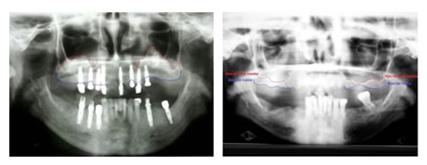

• Caso Clínico Aquí se aprecia la falta de hueso por debajo de los senos maxilares debido a la ausencia de los dientes. Después apreciamos la radiografía donde se hace el procedimiento de elevación de seno maxilar donde se aprecia la colocación del injerto con los implantes ya colocados.

Izquierda: Nótese el injerto colocado obteniendo mayor altura para la colocación de los implantes

Derecha: Aquí se observa la poca cantidad de hueso por debajo de los senos maxilares.